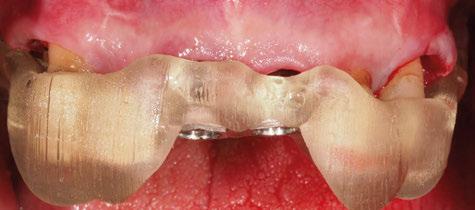

directamente a cabeza de implante para realizar una prótesis dentoalveolar de cerámica de 3 piezas, que equilibraran la oclusión y dieran soporte al labio y la mejilla (Figuras 14-17)

Figura 14. Imagen intraoral frontal postoperatoria al año de la reconstrucción.